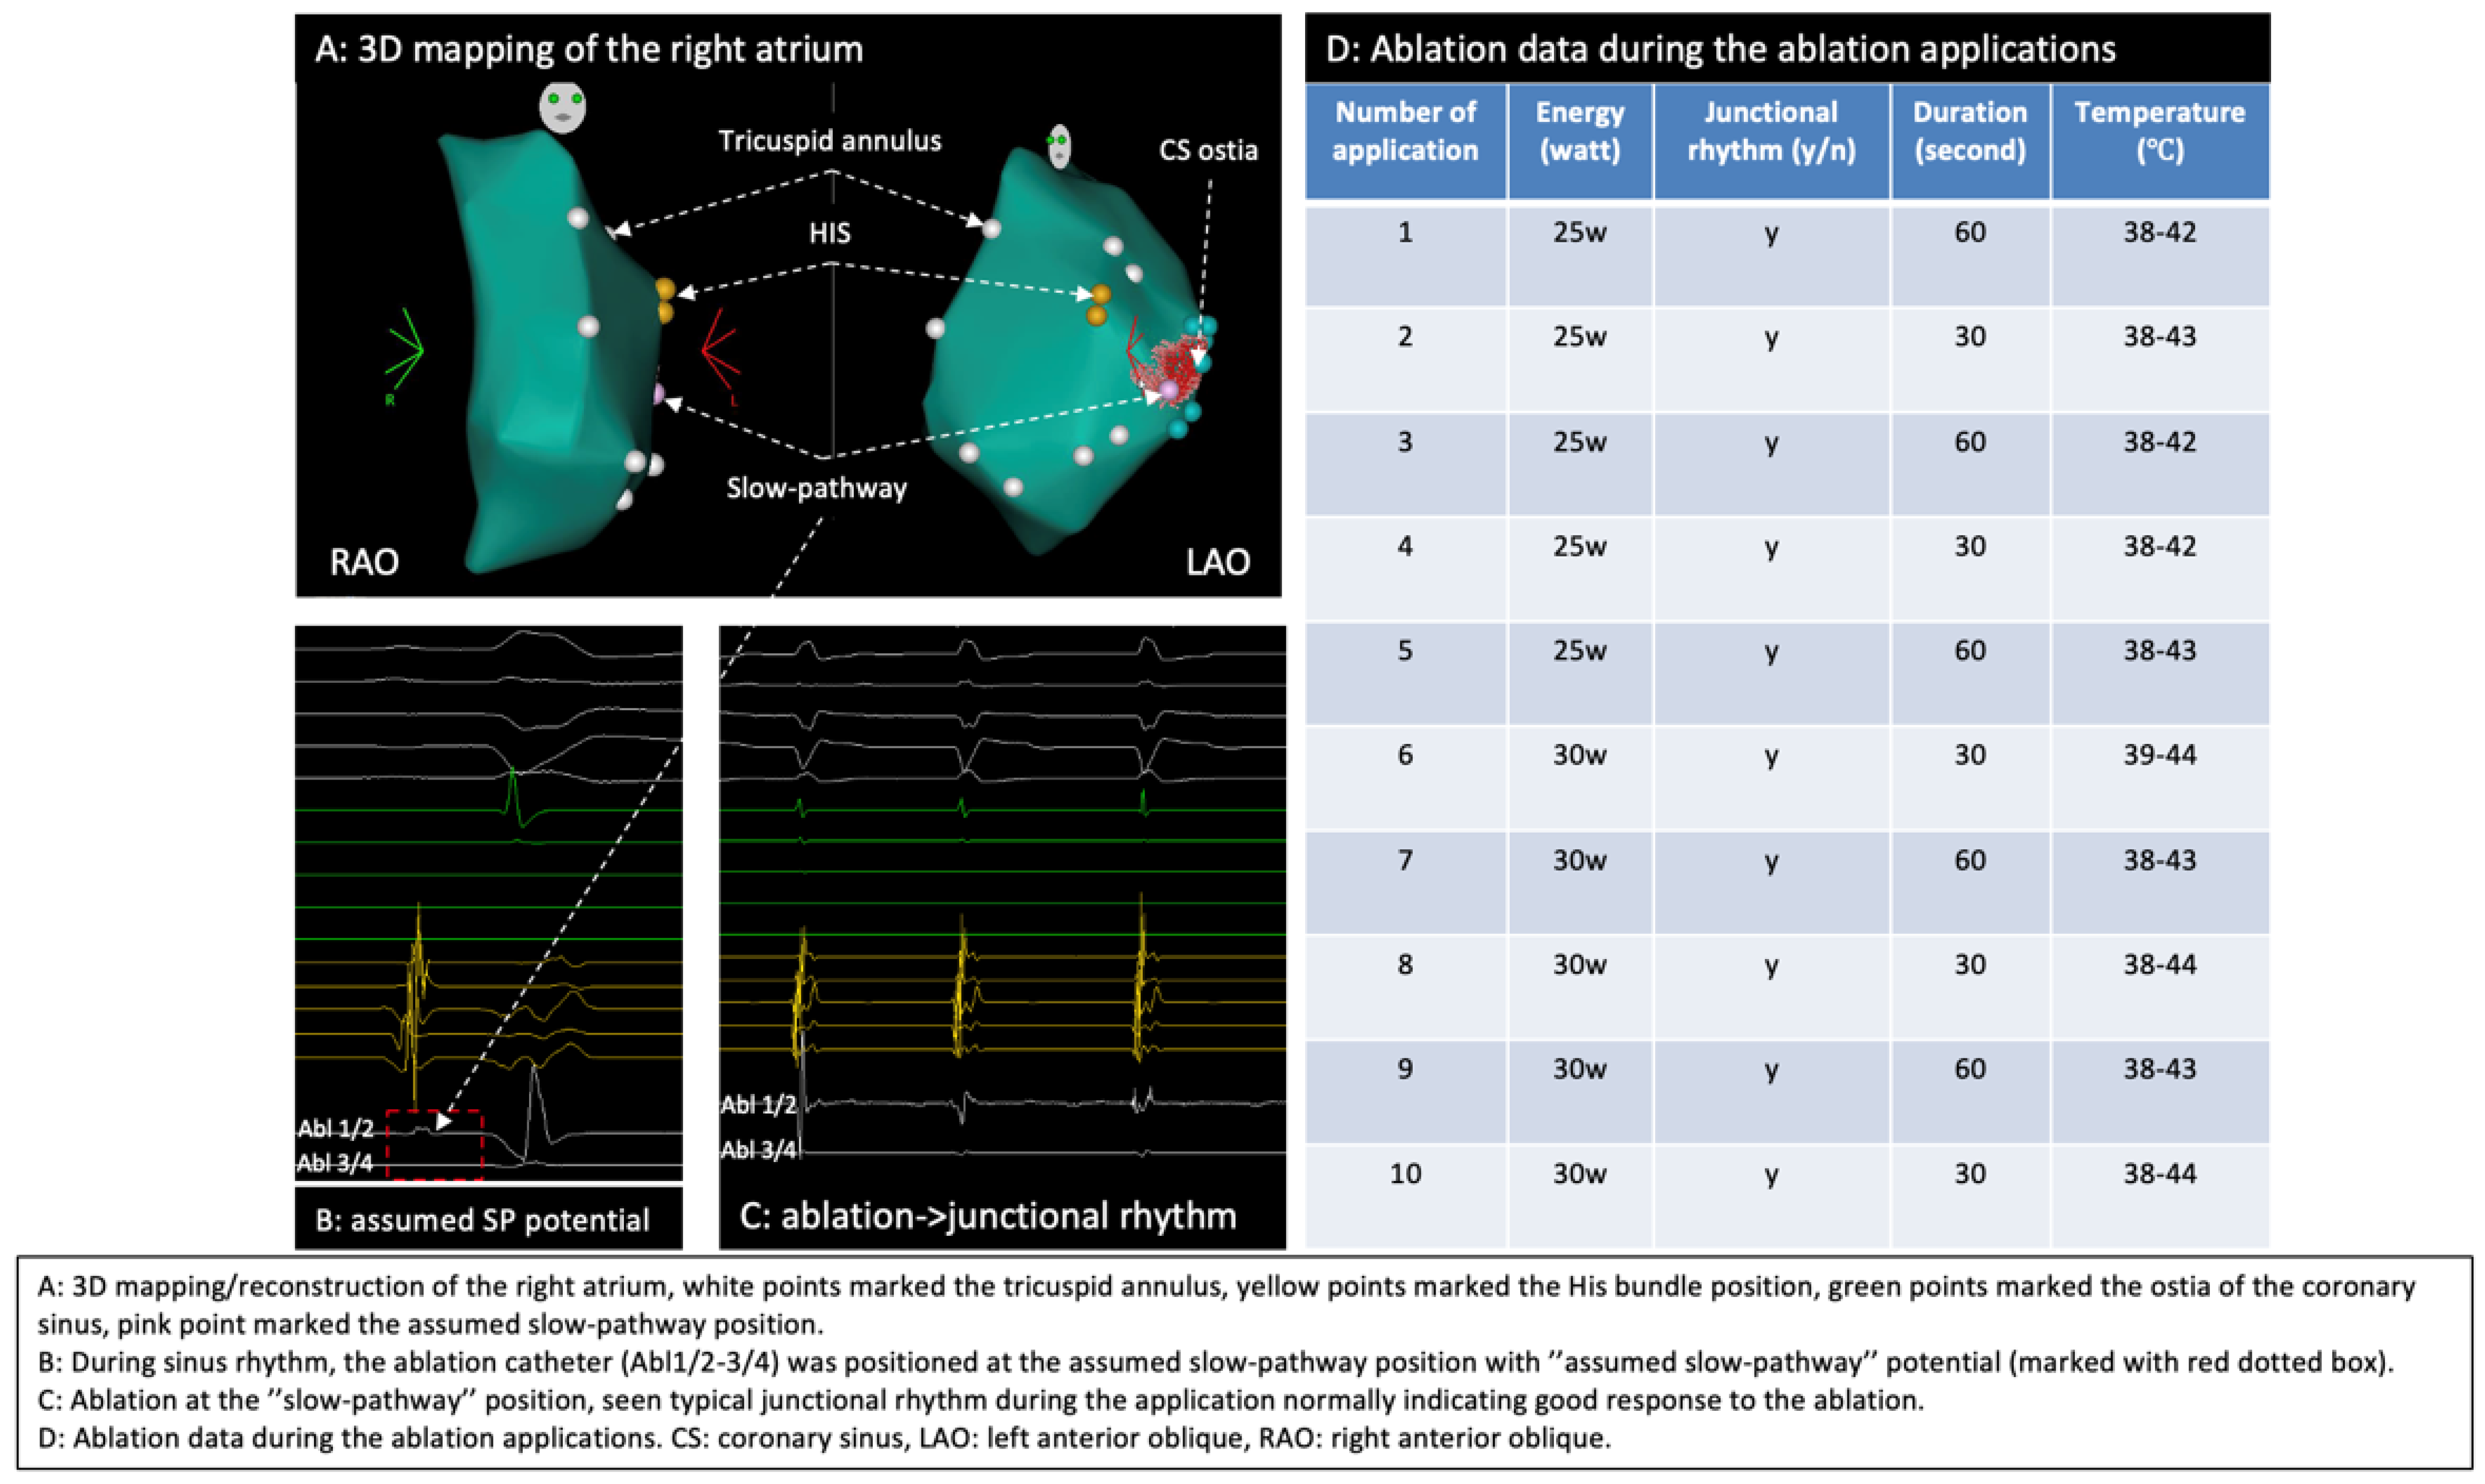

2.3. Ablation Strategy

2.4. Outcome